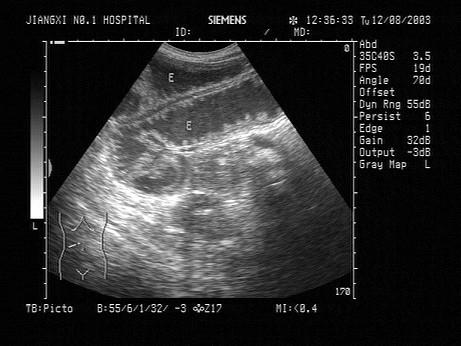

问题 患者,男,42岁,腹痛、呕吐。结合超声声像图,最可能的诊断是?(?)

选项 A.腹膜炎 B.阑尾炎 C.肠梗阻 D.肠道占位 E.肠穿孔

答案 C